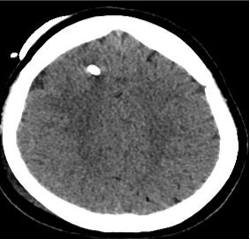

36岁,Chron‘病 和何杰金氏病,同种异体移植,发现右上肺结节,怀疑淋巴瘤复发(replapse)

我们的行动: Our actions:

在ICU In the ICU:

Hare等算法【Hare 2011】的使用实现了快速诊断,加快了决策治疗过程。这是单一案例;然而,由于SAE的罕见性及其危及生命的特点,它更重要。事实上,大多数SAE报告描述了心脏和呼吸道症状【Fiore 2017】,而只有少数报告描述了神经系统表现。

Kim【Kim 2013】等人报道,即使是简单的针插入胸壁,也会导致空气通过肺静脉循环,刺穿肺实质可能不是SAE 的唯一危险操作【Kim 2013】。作者的治疗过程偏离了以前的标准治疗的建议,因为作者的医院没有高压氧腔,从未治疗过SAE。